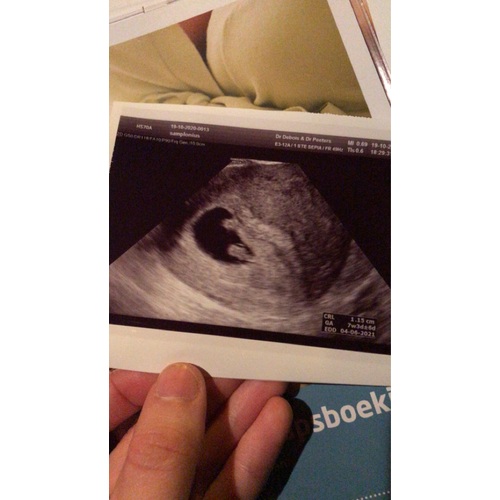

Toevallig dat dit topic nu wordt geopend, ik heb hier vanmorgen namelijk allemaal dingen over zitten opzoeken haha. Maar hoe ik het begrijp (ook op dat andere grote algemene topic gelezen), is het zo dat je moet kijken waar je placenta ligt ten opzichte van het kindje. Je ziet op vroege echo’s nog geen placenta, dus dan moet je kijken naar waar het dooierzakje ligt.

Inwendige echo: placenta/dooierzakje links = meisje, rechts = jongen

Uitwendige echo (is in spiegelbeeld): placenta/dooierzakje links = jongen, rechts = meisje

Volgens die theorie zou ik denken dat ik een meisje krijg, want dooierzakje ligt rechts en het is een uitwendige echo. Maar ik weet het ook allemaal niet zeker, dus als iemand wat anders denkt, hoor ik het ook graag 😊